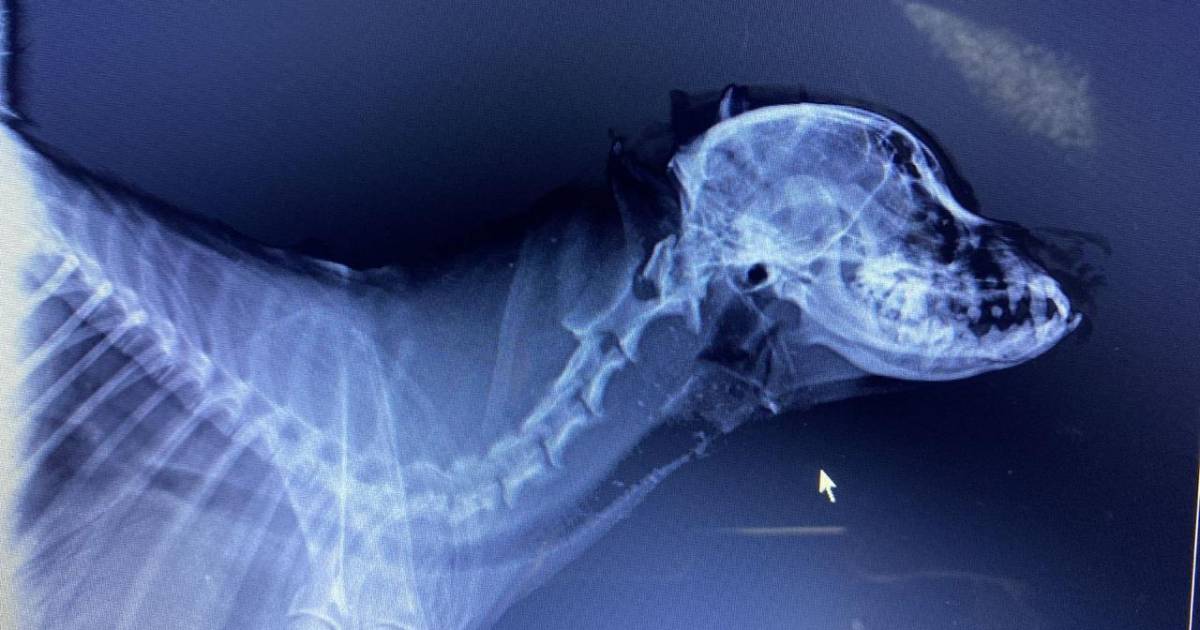

FUERON VARIAS FRACTURAS LAS QUE SE DETECTARON POR ESPECIALISTAS EN EL CRÁNEO DE PAPUCHO

Después de que una vecina de la colonia Emiliano Zapata golpeara en diversas ocasiones a Papucho con un palo de golf, este fue llevado a una veterinaria con apoyo de la Fundación Taraji A.C., especialistas en el tema afirman que la mascota sufrió diversos golpes que causaron la inflamación de su cerebro, por lo tanto continúa paralizado.

“Como conclusión a la imagen en pocas palabras se ve que fueron varios impactos, no solo uno, asi lo demuestran los rayos x” dijo el veterinario a Oscar Zamora Bustos su dueño.

Expuso que tiene al menos golpe en el maxilar superior, en cráneo y en el axis, a raíz de esto tiene toda la cabeza interna inflamada, desde el cerebro hasta el esófago.